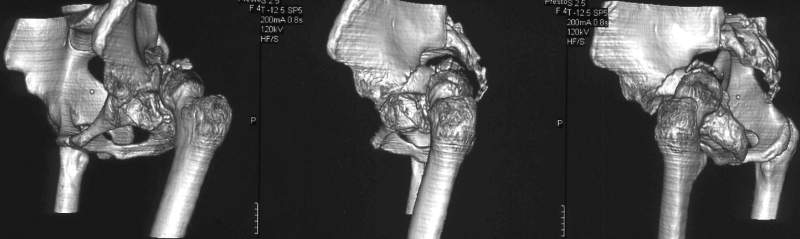

важаемые коллеги,пациент 23 лет (вес 75 кг), обратился к нам по поводу боли в тазобедренном суставе при ходьбе, нестабильность в нем при нагрузке. Ходит с тростью. 8 мес. назад попал в ДТП (никаких медицинских документов у него нет). Стоит ли открываться и вправлять вывих или сразу делать бесцементное тотальное эндопротезирование? С уважением, А. В. Вакуленко Клиника эндопротезирования суставов, г. ДонецкDear All, male patient 23 y.o., body weight 75 kg. Had RTA 8 months ago (medical records unavailable). Now has pain on motion in his left hip. On weight-bearing hip is unstable (patient use cane while walking). Keeping in mind his age, is it worth to perform open reduction? Or just do uncemented THR? Any comments are very welcome.

After 8 months, the hip will not easily come down into the acetabulum. It also appears to me that there is an impression fracture of the head of femur.

Здравствуйте. Позвольте поучаствовать в обсуждении. Поскольку пациент в течение 8 месяцев не получил адекватного лечения (видимо и по своей вине тоже), а также учитывая удовлетворительное состояние головки бедра(по данным КТ), есть смысл выполнить открытое вправление головки бедра с возможной фиксацией фрагмента заднего края пластиной. Далее начать восстановление функции сустава, дозированную нагрузку. Возможно молодой возраст пациента поможет ему отдалить время эндопротезирования. Желаю успехов.